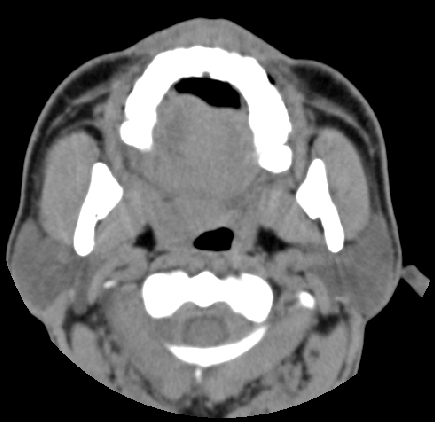

男性 49岁 劳累精神紧张后感咽部不适,疼痛,查:右上鄂肿胀

右侧扁桃腺肿大,但与周围组织分解清晰,考虑炎性

根据病史是慢性反复发作的吧的吧,病灶还比较局限,考虑慢性咽炎扁桃体炎可能性大

右侧腭扁桃体肿大,原因待查;建议行进一步检查排除肿瘤性病变可能。